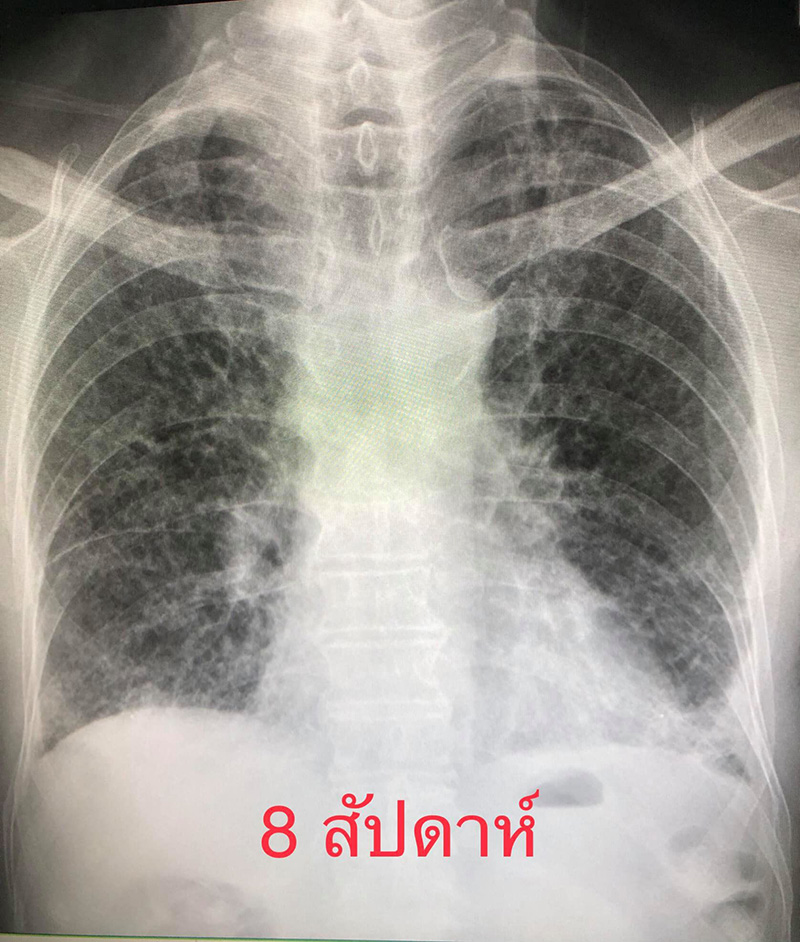

หลังจากติดโควิด-19 ได้ 8 สัปดาห์ ก็มีไอเล็กน้อย ไม่มีไข้ เดินนิดเดียวก็เหนื่อย ต้องใช้ออกซิเจน 4 ลิตรต่อนาทีตลอดเวลา ถึงระดับออกซิเจนในเลือดจะมาอยู่ที่ 95% ถ้าไม่ใช้ออกซิเจนช่วยจะลดลงต่ำกว่า 80%